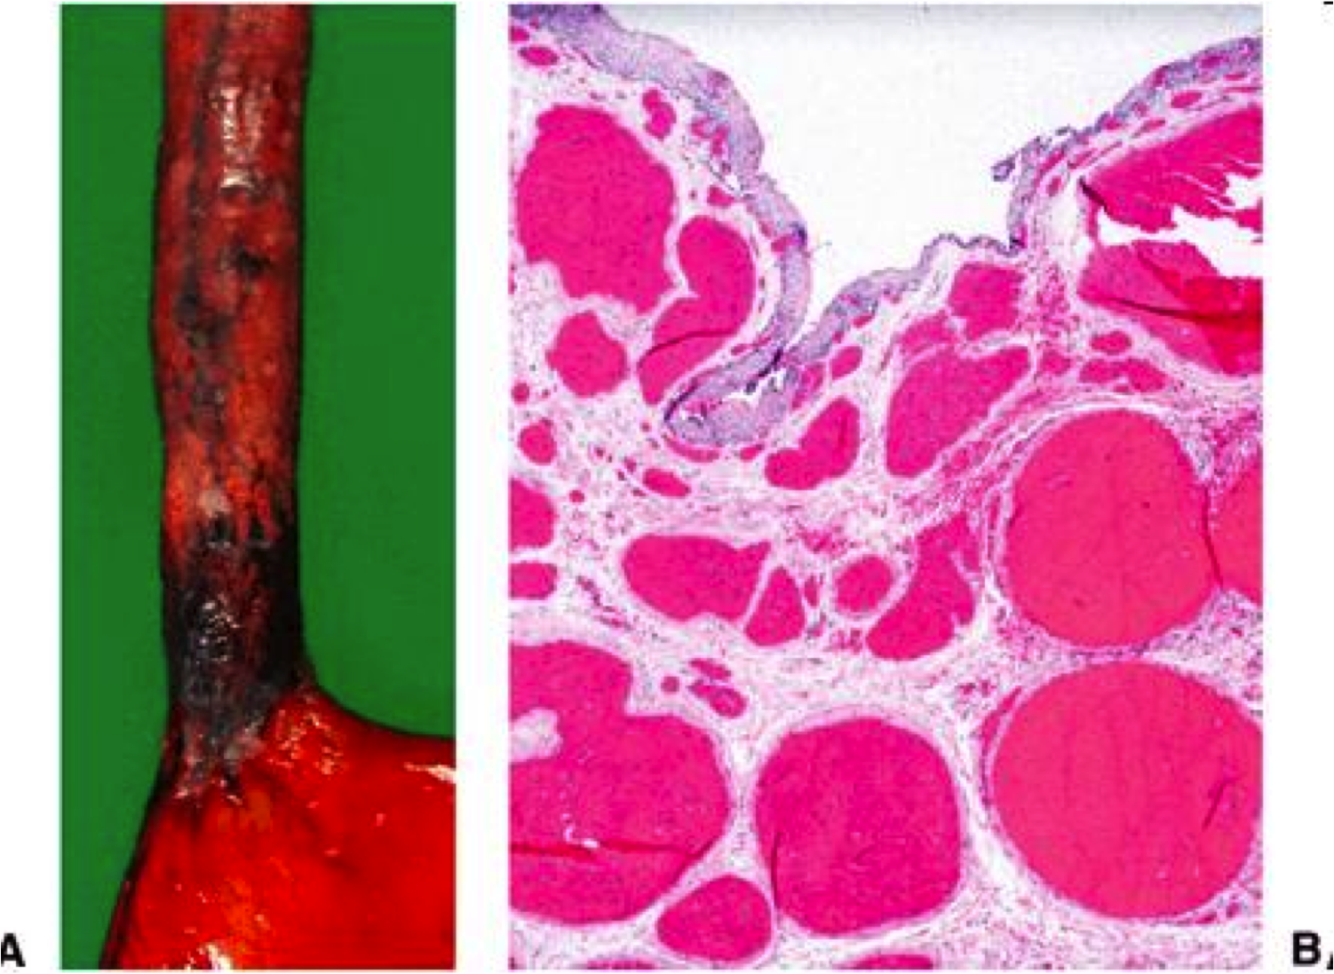

esophageal varices: Dilatation of submucosal esophageal veins

most often due to portal hypertension secondary to cirrhosis

- *Mallory-Weiss laceration**

- at GE junction (usually on gastric side)

- Forceful vomiting/retching forces prox stomach through diaphragm

- Laceration may bleed profusely

- Acute esophageal rupture –> Boerhaave’s syndrome